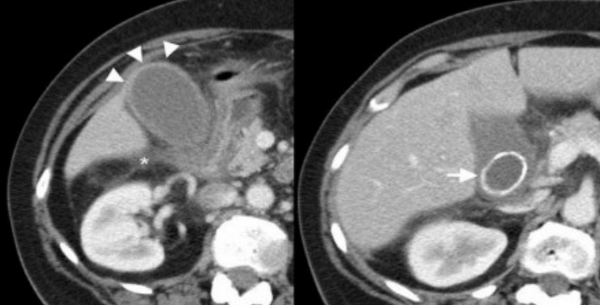

(Левый) При КТ с контрастным усилением у пациента с острым бескаменным холециститом визуализируются растянутый желчный пузырь с утолщенной стенкой, скопление перипузырной жидкости и воспаление перипузырной жировой клетчатки. Обратите внимание на слабое контрастирование стенки в области дна желчного пузыря.

(Правый) На поперечном УЗ срезе у пациента с бескаменным холециститом определяется сладж, утолщение стенки и чрескожный холецистостомический дренаж. Также видно скопление перипузырной жидкости.